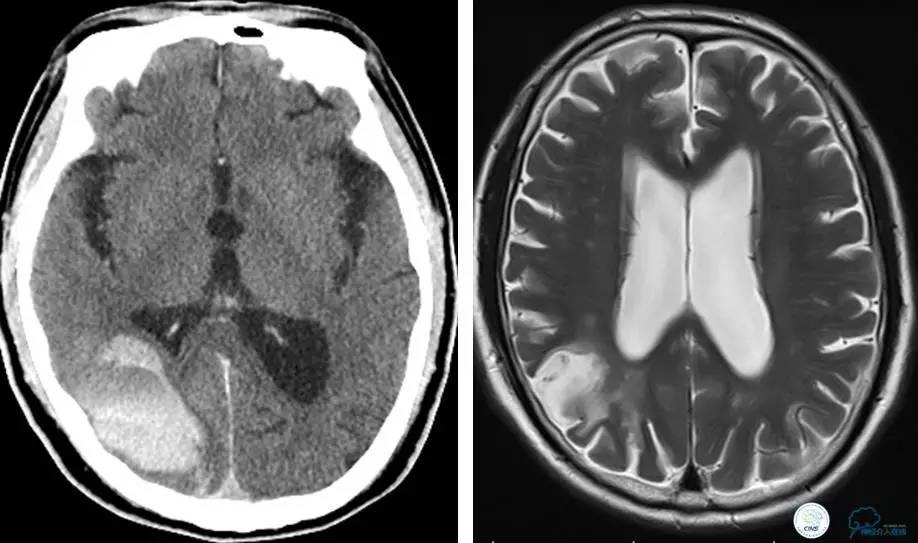

▼术后即刻CT,梗死灶内再灌注出血。

患者无症状,中性治疗。4月21日电话随访,一般情况好,当地CT示出血吸收期。

患者:49岁男性,左侧偏瘫1个月,药物治疗、康复训练效果不好,转我院,肌力0~1级。

core-clilnical明显不匹配,是介入开通的合适患者。

术后即刻和6天后CT,患者无明显临床症状。

半年后复查造影,无支架内再狭窄,可见弹簧圈,患者恢复至自己柱杖行走。